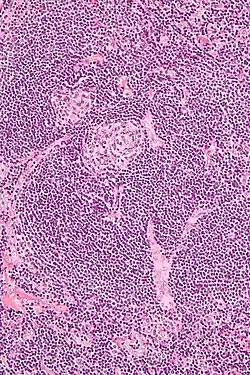

Micrograph of lymph node biopsy demonstrating hyaline vascular features consistent with Castleman disease | |

The microscopic appearance (histology) of biopsied tissue from an enlarged lymph node must demonstrate a constellation of features consistent with Castleman disease. There are three patterns of characteristic histologic features associated with iMCD:[5]

- Hypervascular - regressed germinal centers, follicular dendritic cell prominence, hypervascularity in interfollicular regions, and prominent mantle zones with an “onion-skin” appearance.

- Plasmacytic – increased number of follicles with large hyperplastic germinal centers and sheet-like plasmacytosis (increased number of plasma cells).

- Mixed – features of both hypervascular and plasmacytic.

iMCD most commonly demonstrates plasmacytic features; however, hypervascular features or a mixture of both hypervascular and plasmacytic features may also be seen in iMCD lymph nodes. The clinical utility of subtyping iMCD by histologic features is uncertain, as histologic subtypes do not consistently predict disease severity or treatment response.